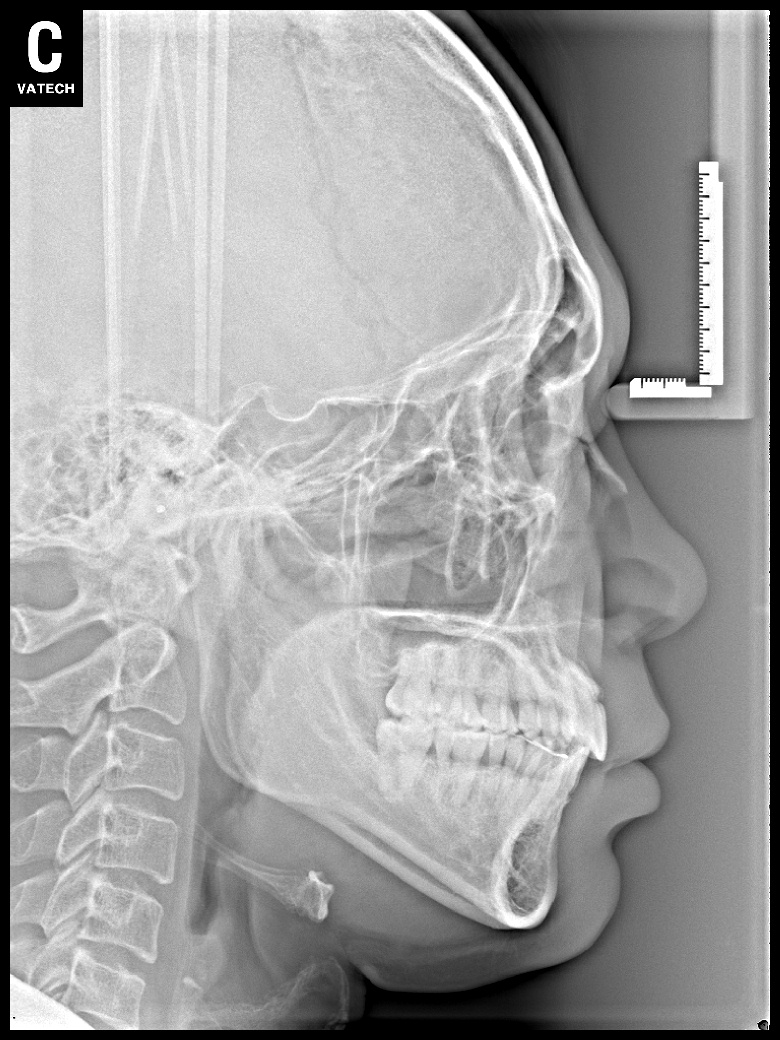

[돌출입] 돌출입